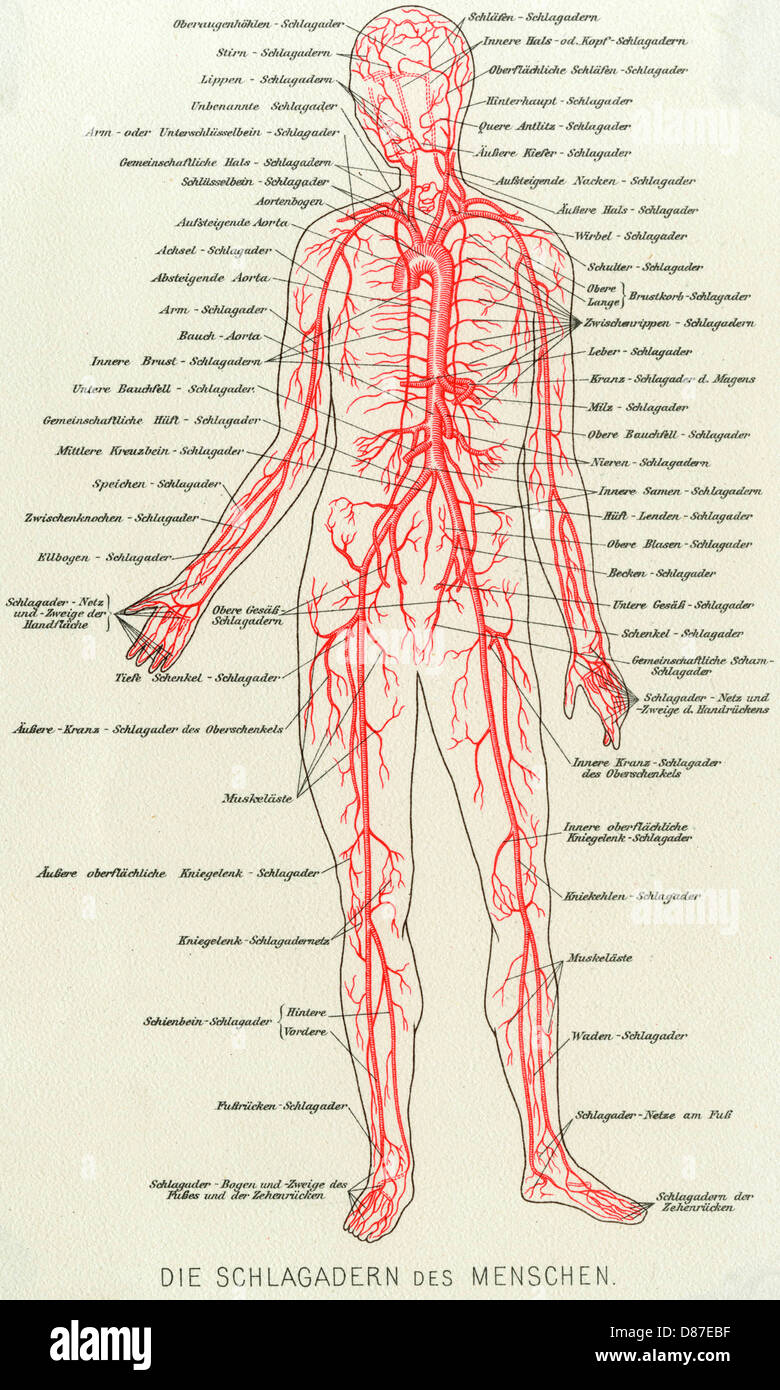

MÉDICAL/ANATOMIE/SANG Banque D'Imageshttps://www.alamyimages.fr/image-license-details/?v=1https://www.alamyimages.fr/photo-image-medical-anatomie-sang-56713315.html

MÉDICAL/ANATOMIE/SANG Banque D'Imageshttps://www.alamyimages.fr/image-license-details/?v=1https://www.alamyimages.fr/photo-image-medical-anatomie-sang-56713315.htmlRMD87EBF–MÉDICAL/ANATOMIE/SANG